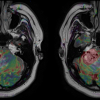

July 3, 2017 — When diagnosing strokes and heart diseases or looking at tumors, perfusion magnetic resonance imaging (MRI) offers a gentler way to capture the blood flow circulation in the organs. However, the method is far from being implemented to its full potential at many clinics. The Fraunhofer Institute for Medical Image Computing MEVIS in Bremen, Germany organized a workshop entitled “Measurement of Perfusion and Capillary Exchange” from June 21-23 to promote adoption of the method. The event provided information about its applications and the current state of research.

MRI allows a gentler way of taking 3-D images of the inside the body. One specific variant is perfusion MRI. It visualizes the perfusion of organs and tumors. “Perfusion measurements deliver important information about an organ’s condition,” said Fraunhofer MEVIS researcher and workshop initiator Matthias Günther. “It enables clinicians to diagnose at an early stage how well an organ is functioning.”